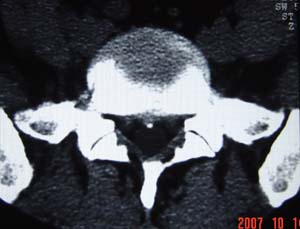

本人的片子,腰腿痛多年,时轻时重。请各位老师发表高见!

1.l4~5间盘膨出伴突出(中央型)

2.l5-s1后纵韧带钙化.

测量应该测上一层面,。支持诊断。